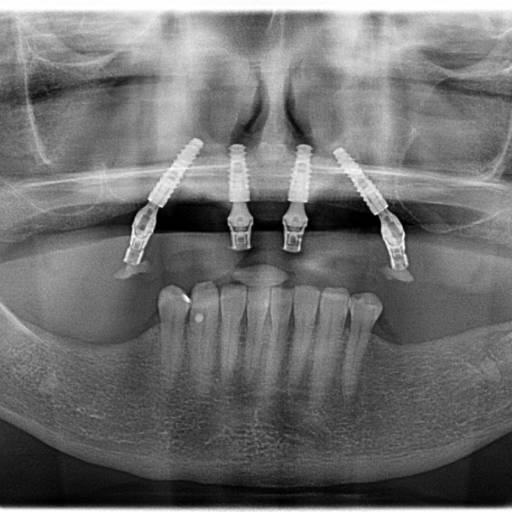

Na Medeiros Odontologia, oferecemos uma variedade de serviços que cobrem todas as necessidades odontológicas, desde cuidados preventivos até tratamentos complexos. Nosso principal destaque é o Implante Zigomático, ideal para pacientes com perda óssea significativa. Outros serviços incluem:

- Protocolo All On 4: Uma técnica avançada para quem busca próteses dentárias fixas.